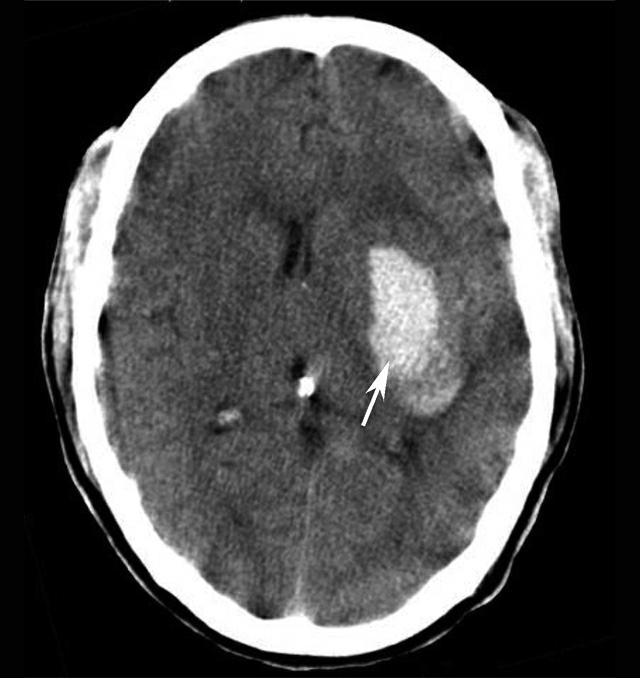

图1-2-20 环池闭塞

右侧颞叶脑内大血肿(★),产生严重的占位效应,环池受压闭塞(箭),脑疝形成